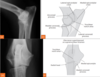

82

Review mediolateral dog stifle joint anatomy.

Review craniocaudal dog stifle joint anatomy.